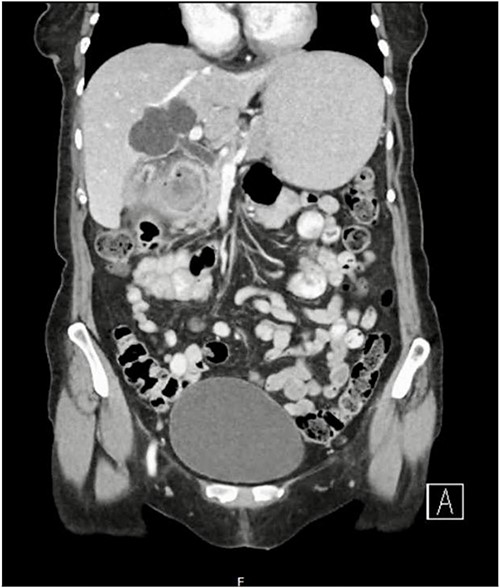

A 79-year-old female presented with a 5-day history of nausea, vomiting, and abdominal discomfort but no overt pain. She was hemodynamically stable. On examination, she had mild right upper quadrant tenderness but no signs of peritonism and a negative Murphy’s sign. Computed tomography (CT) of the abdomen and pelvis revealed features suggestive of acute cholecystitis, complicated by cholecystoduodenal fistula with a large (3.5 cm) gallstone impacted at the second part of the duodenum (Figs 1 and 2), consistent with Bouveret syndrome. The patient was kept fasting and a nasogastric tube was inserted for gastric decompression. She underwent a gastroscopy in an attempt to remove the impacted gallstone. However, the stone could not be retrieved due to its severe impaction, most evident on the pylorus side of the duodenum (Fig. 3).

Axial CT image of abdomen demonstrating a fistulous connection between the gallbladder and duodenum and a large gallstone.